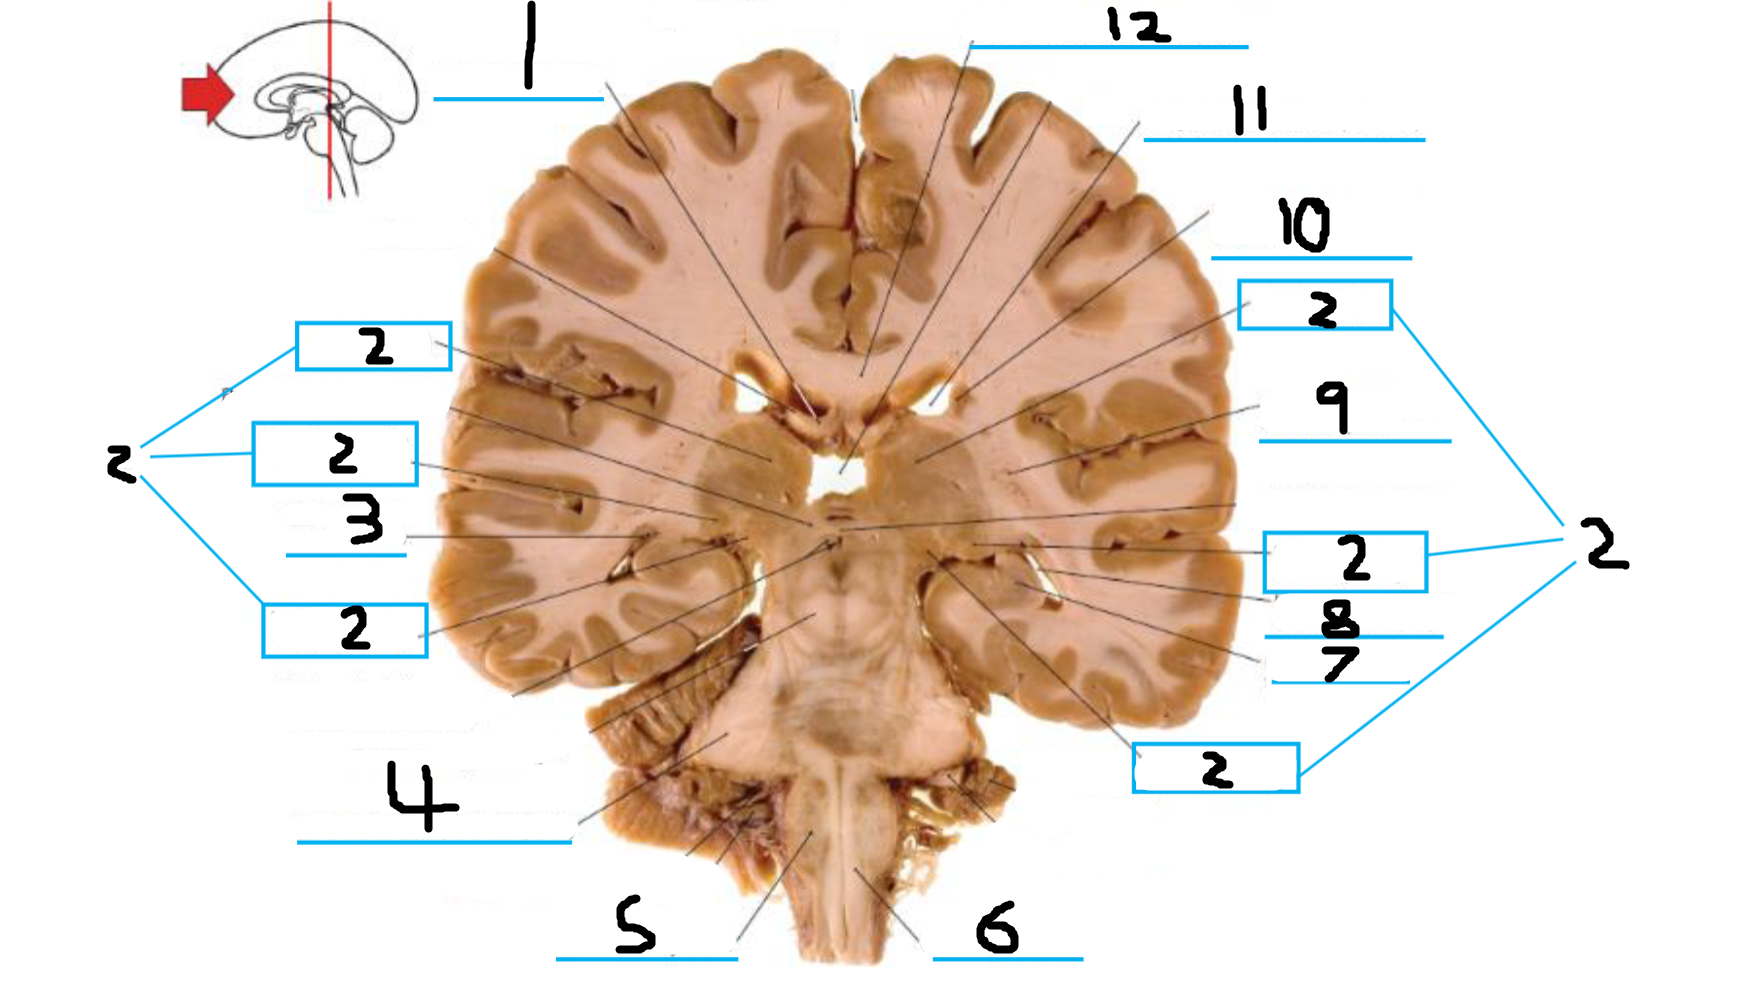

#1 is the:

Corpus Callosum

#2 is the:

Septum Pellucidum

#3 is the:

Lateral Ventricle

#4 and #9 is the:

Globus Pallidus

#5 is the:

Insula

#6 and #8 is the:

Anterior Commissure

#7 is the:

Optic Chiasm

#10 is the:

Putamen

#11 is the:

Internal Capsule

#12 is the:

Caudate